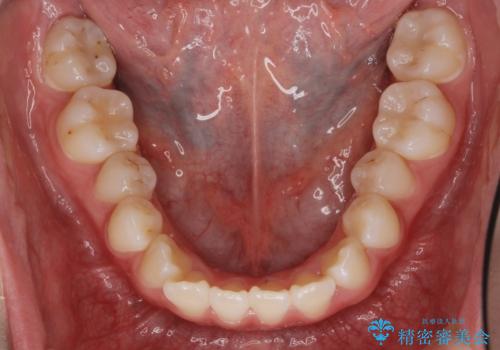

下の小臼歯を抜歯しましたが、その代わり下の親知らずを残して咬ませたので、歯の数は変わっていません。

親知らずが歯ぐきに埋まっていると不潔になり、炎症を繰り返すため残しておくことが難しい場合が多いです。

今回は左下の小臼歯を1本抜歯してるのと、手術を行なって親知らずを顎に収めることができました。